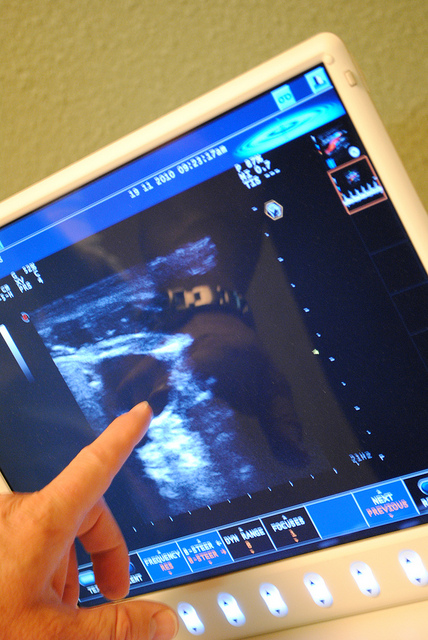

Принцип работы УЗИ схож с работой радиолокации. Суть в том, что при исследовании подаются волны. Они, отражаясь от органов и тканей, дают картину об их расположении и форме. На экран выводится изображение благодаря специальному датчику. Такая процедура не представляет опасности для здоровья, поэтому не обладает противопоказаниями. Важно только, сколько стоит УЗИ брюшной полости, хотя в большинстве случаев это доступная процедура.

Благодаря УЗИ можно отслеживать процесс беременности, видеть размещение плода.